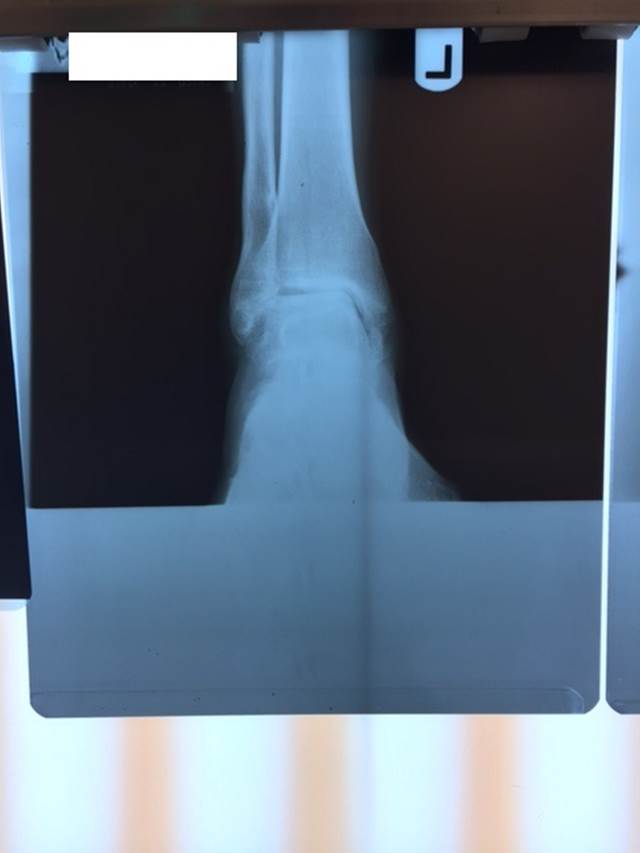

"Surgical misadventure" by another surgeon about 8 years ago. The wrong fixation was used for a flatfoot repair, & the deformity was not corrected. Patient came in with severe foot & ankle pain, with no arch at all. She was unable to play with her grandchild because the pain was so bad, & because she felt unsteady. The old hardware was removed, a lateral calcaneal lengthening osteotomy was performed along with a medial column/1st ray realignment. The ankle was painfully arthritic, & patient elected a total ankle replacement vs. an ankle fusion. She is now able to walk pain free & play with her grandchildren!